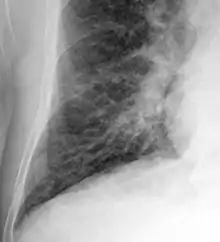

Chest X-rays are frequently used to aid in the diagnosis of CHF. In a person who is compensated, this may show cardiomegaly (visible enlargement of the heart), quantified as the cardiothoracic ratio (proportion of the heart size to the chest). In left ventricular failure, evidence may exist of vascular redistribution (upper lobe blood diversion or cephalization), Kerley lines, cuffing of the areas around the bronchi, and interstitial edema. Ultrasound of the lung may also be able to detect Kerley lines.[69]

Congestive heart failure with small bilateral effusions

Kerley B lines